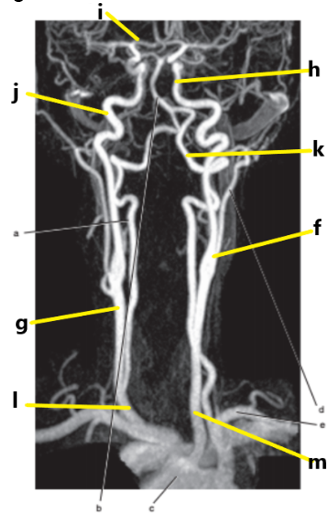

What is letter l ?

Common carotid

What is letter e ?

Subclavian artery

What is letter f ?

Common carotid artery

What is letter i ?

Anterior cerebral artery

What is letter m ?

What is letter j ?

Internal carotid artery

What is letter g ?

Vertebral artery

Aortic arch

What is letter b ?

What is letter k ?